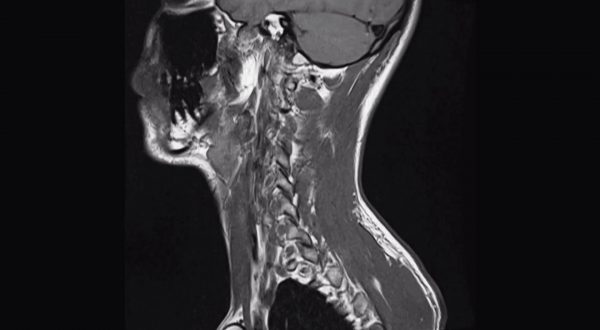

Tumori dell’orofaringe in aumento, i segnali da non sottovalutare